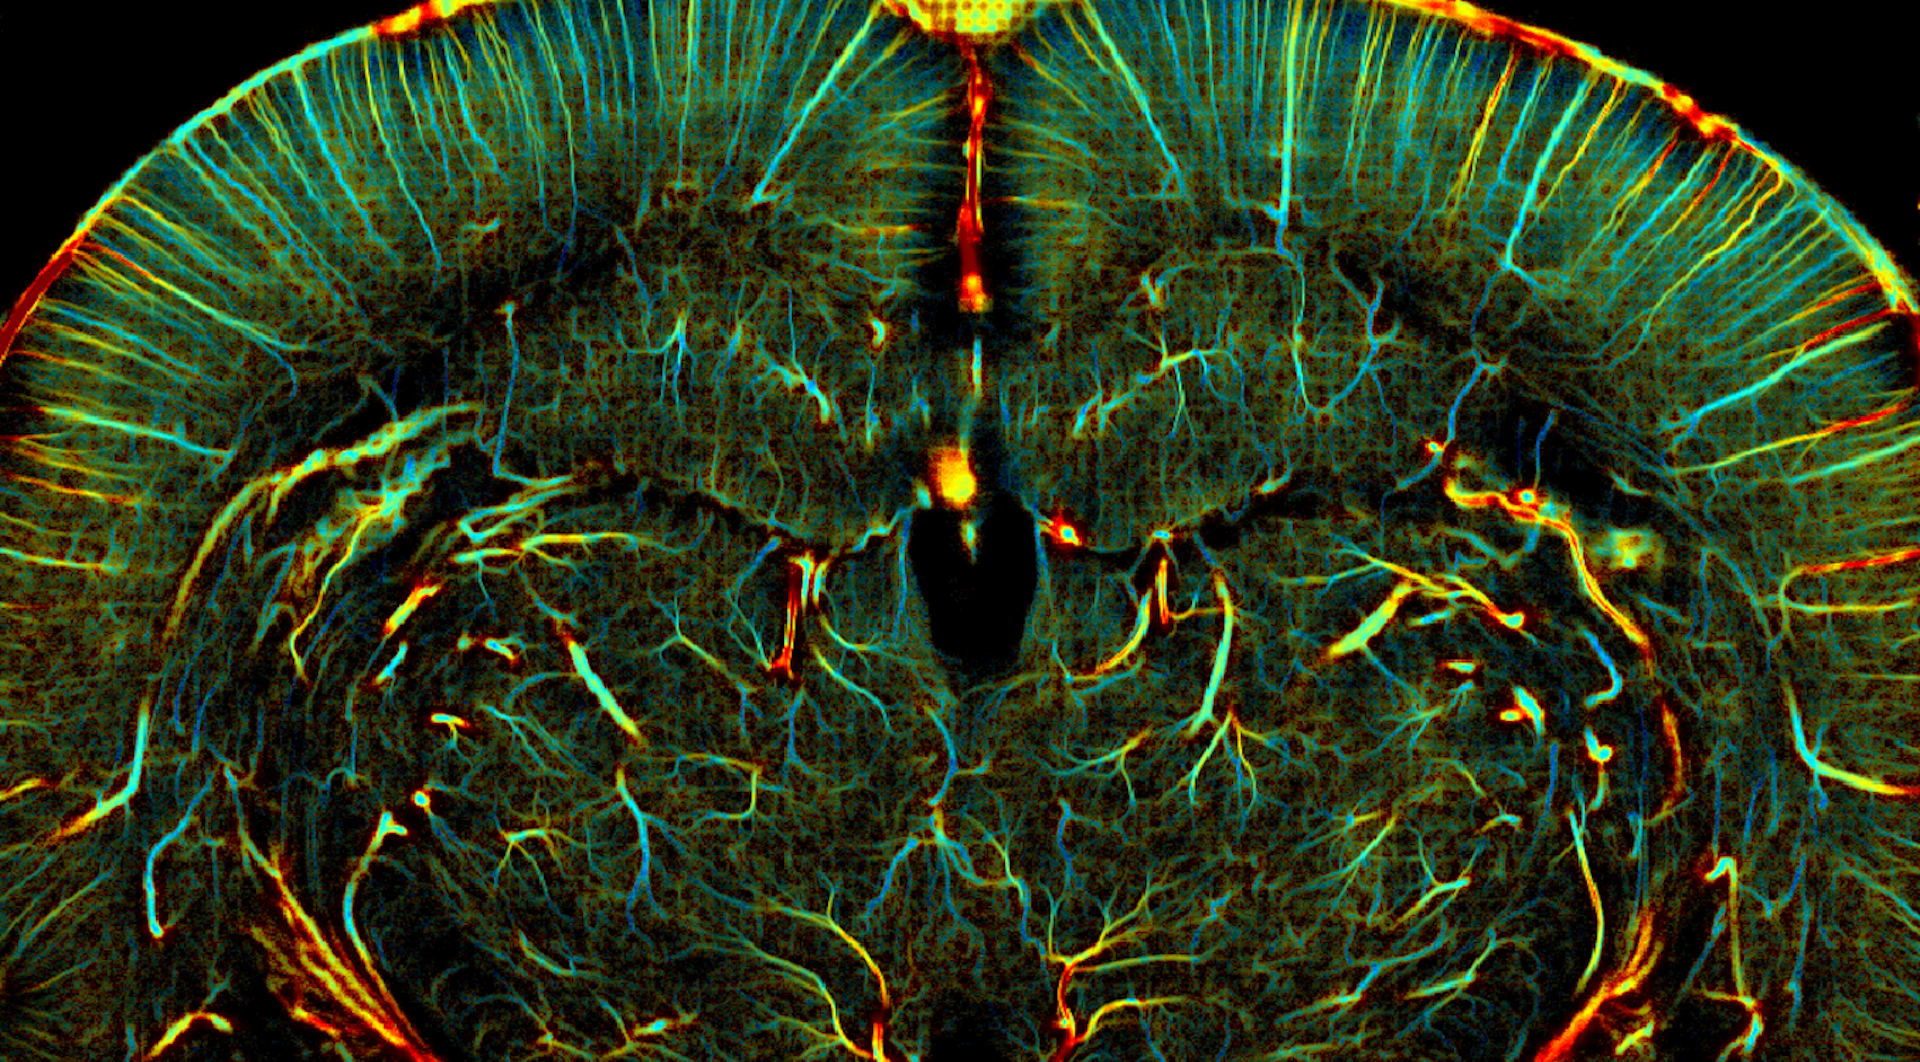

Cette résolution microscopique peut être atteinte par l’imagerie de super-résolution ultrasonore grâce à l’injection intraveineuse de microbulles – une injection inoffensive et déjà utilisée en routine clinique pour améliorer le contraste des échographies classiques. Dans notre cas, grâce à l’échographie ultrarapide, chaque microbulle et sa trajectoire dans le sang sont mesurées avec une précision 100 fois meilleure qu’en échographie conventionnelle, résultant en un film unique – jusqu’à l’échelle microscopique – des flux sanguins. Une acquisition de quelques secondes suffit à accumuler une quantité d’informations astronomique, donnant accès à la vitesse et la direction des flux sanguins à chaque endroit du cerveau, des grosses artères jusqu’aux vaisseaux de quelques microns de diamètre. Déjà validée chez l’animal et en cours de développement chez l’humain, l’imagerie de super-résolution ultrasonore permettra bientôt au médecin de naviguer en temps réel dans le cerveau du patient, et de zoomer à loisir jusqu’à l’échelle microscopique à la recherche de signes précurseurs de pathologies cérébro-vasculaires.